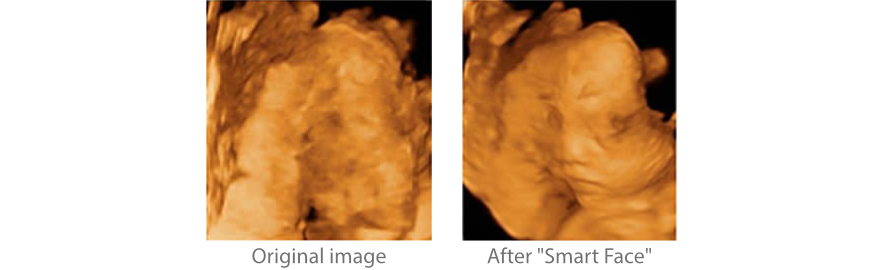

Smart Face

Yeni Z60, tek dokunu?la fetal yÞz i?in h?zl? ve ak?ll? optimizasyon sa?lar. Hacim verilerinde oklÞzyonlar? an?nda kald?rabilir, istenmeyen gÞrÞltÞ bilgilerini ortadan kald?rabilir ve minimum i?lemle fetal yÞzÞn optimum g?rÞnÞmÞnÞ olu?turabilir.